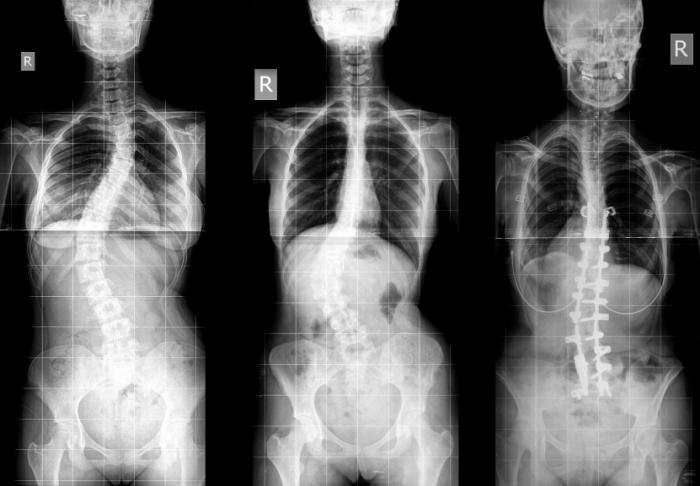

Skolyoz, omurganın göğüs veya bel bölgelerinde görülebilen, yana doğru eğriliğidir. Normal ve sağlıklı omurgada omurlar arkadan bakıldığında yukardan aşağıya yani boyun, sırt ve bel bölgelerinde düz bir hat şeklinde uzanır. Skolyozda ise omurlar sağa veya sola doğru yer değiştirir ve aynı zamanda kendi eksenleri etrafında skolyoz omurga döner.

Omurgaya arkadan bakıldığında eğrilik düz durulduğunda bile fark edilebildiği gibi bazen bu denli net değildir ve ancak öne eğilme durumunda, kontroller ve röntgen filmlerinde anlaşılabilir.